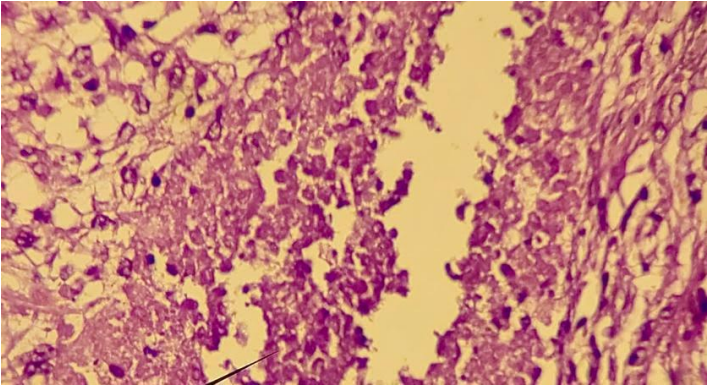

Quantiferon assay not performed in all patients, examination not available in the regional hospital. HIV serology: all our patients benefited from a rapid HIV test, it was positive in 2 patients, the confirmation carried out by serology. Bacteriological and histological confirmation carried out after exploratory cervicotomy objectifying an epitheliogigant granuloma in all our patients; None of our patients have benefited from a needle aspiration. The expert gene study carried out in all patients looking for resistance did not objectify any case of resistance.(figure 3).

Figure 3: histoligical blade showing the epitheliogigant granuloma

All our patients had benefited from an exploratory cervicotomy with an incision that depended on the site of the lymphadenopathy. For the evolution under antibacillary medical treatment was marked by a paradoxical reaction in two patients and a prodigious scar in 5 patients.